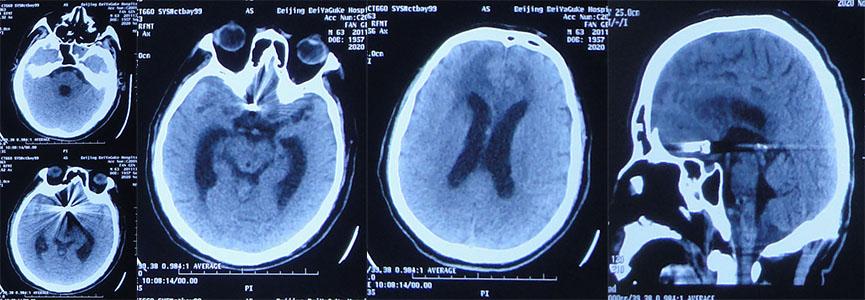

患者2020年10月16日6时30分晨起突发头晕呕吐,伴有意识不清,家属拨打120,将其送入山西省运城市某医院,急诊查头部CT示额叶脑出血伴广泛蛛网膜下腔出血、脑室内铸型( 图-1 );住入重症病房。

图-1: 2020年10月16日头部CT:额叶脑出血伴广泛蛛网膜下腔出血、脑室内铸型